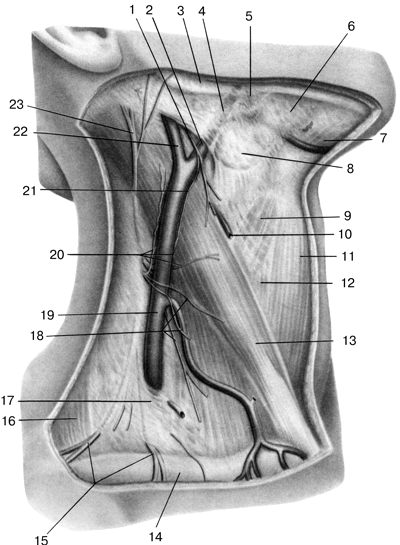

Анатомия внутренней яремной вены: КТ изображения